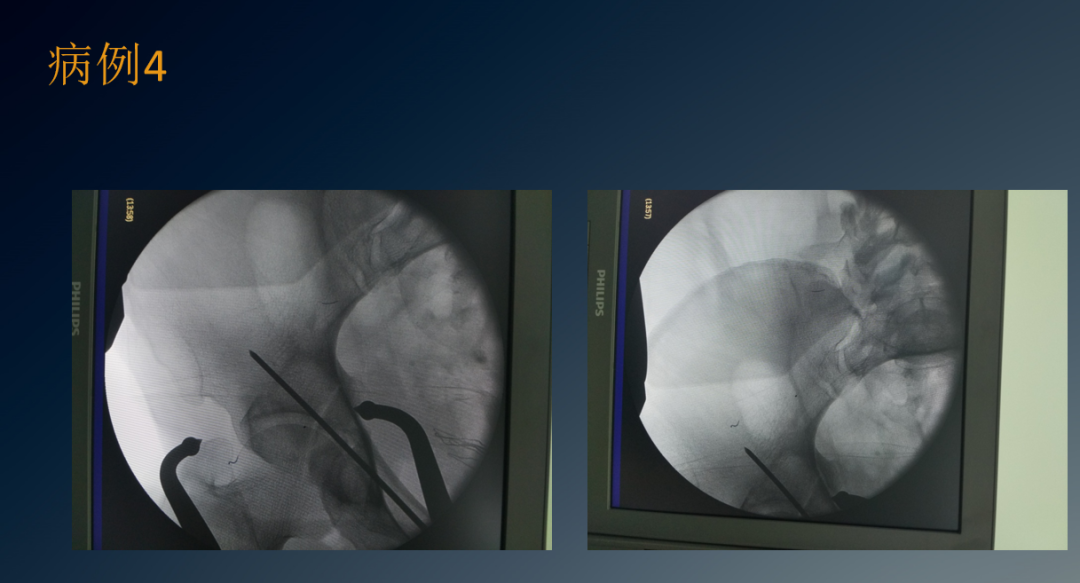

临床病例